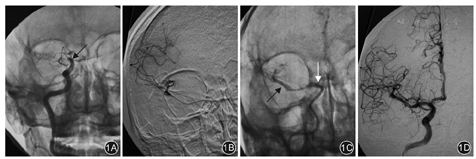

术后84例患者均获随访3个月。随访期间,观察组43例中,发生颅内出血2例(4.88%),死亡2例(4.88%),后者中1例术后大量脑出血脑疝死亡、另1例术后3天突发下壁心梗死亡;对照组41例中发生颅内出血9例(19.51%),死亡4例(9.76%),后者中2例术后大量脑出血脑疝死亡、1例大面积脑梗死脑疝死亡、1例术后肺部感染死亡。观察组颅内出血率低于对照组,差异有统计学意义(χ2=5.520,P<0.05);而两组死亡率差异无统计学意义(P>0.05)。两组患者术后1周NIHSS评分均较术前降低,且观察组NIHSS评分低于对照组,差异均有统计学意义(P值均<0.01),见表3。术后3个月采用mRS评估患者预后情况,观察组预后良好31例、不良10例,对照组预后良好20例、不良17例,观察组预后良好率为75.61%(31/43),优于对照组的54.05%(20/37),差异有统计学意义(χ2=3.993,P<0.05)。典型病例见图1。